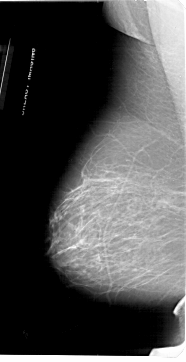

ics_version 1.0 filename A-1953-1 DATE_OF_STUDY 9 6 1992 PATIENT_AGE 50 FILM FILM_TYPE REGULAR DENSITY 2 DATE_DIGITIZED 4 3 1999 DIGITIZER HOWTEK 43.5 SEQUENCE LEFT_CC LINES 6871 PIXELS_PER_LINE 3361 BITS_PER_PIXEL 12 RESOLUTION 43.5 NON_OVERLAY LEFT_MLO LINES 6871 PIXELS_PER_LINE 3526 BITS_PER_PIXEL 12 RESOLUTION 43.5 NON_OVERLAY RIGHT_CC LINES 6616 PIXELS_PER_LINE 3436 BITS_PER_PIXEL 12 RESOLUTION 43.5 OVERLAY RIGHT_MLO LINES 6871 PIXELS_PER_LINE 3631 BITS_PER_PIXEL 12 RESOLUTION 43.5 OVERLAY |